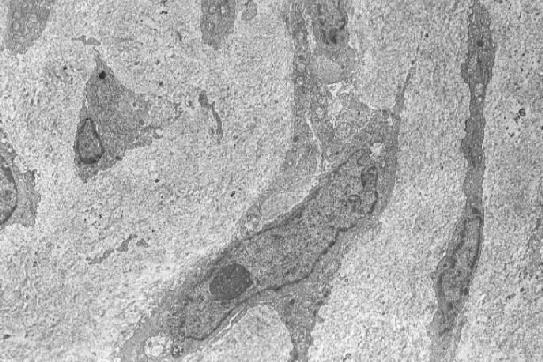

Operation specimen (jpg.20KB) (OMH 98-0339): Primary pulmonary artery sarcoma, open thoracic surgery - intimal sarcoma (HE stain [jpg.44KB]), with involvement of the pulmonary valve. Electron microscopic examination reveals elongated cells (jpg.52KB) and occasionally multipolar giant cells (jpg.75KB) with irregulary indented nuclei, whose cytoplasm contains electron-dense inclusion bodies that measure 500 nm in largest diameter (jpg.46KB), suggesting of lysozomal origin but being somewhat similar to neurosecretory granules. No basal lamina is formed near the tumor cells.